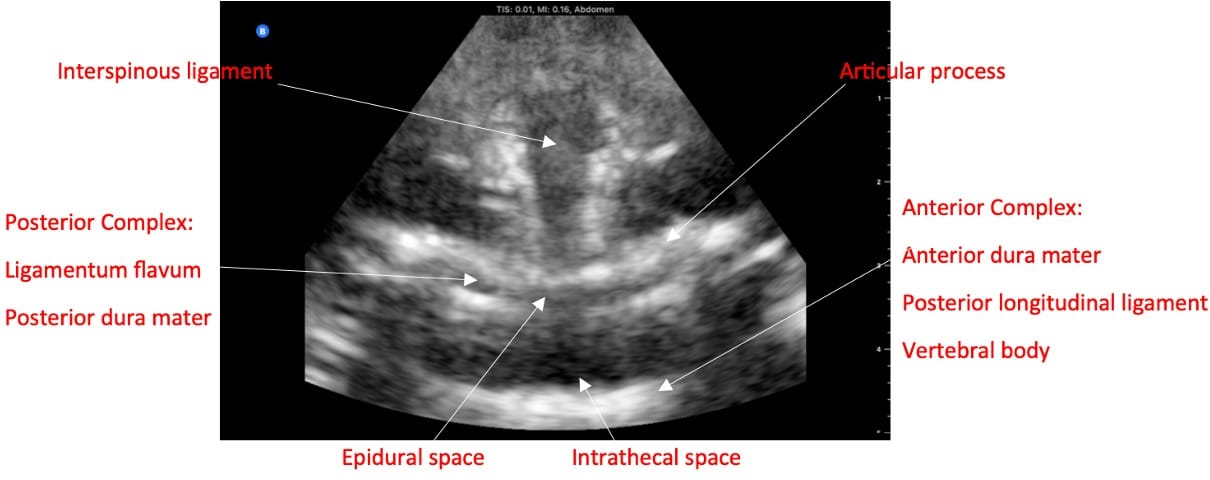

If the clinician does not have access to a dedicated ultrasound, they can use the obstetric ultrasound, which has the curvilinear probe.37 In the paramedian sagittal view, the sacrum appears as a flat, hyperechoic structure. The lamina and interspaces are visualized by scanning in a cephalad direction (Video 13). In transverse view, note that when the probe is on a spinous process, a dark acoustic shadow is present.38 Once scanning within an interspace and with possible tilting of the probe, one can visualize the ligaments, articular processes, and sometimes transverse processes (Figure 5). Ligamentum flavum and posterior dura mater often appear as a single hyperechoic line called the posterior complex. The dark band anterior to the posterior complex is the intrathecal space, as cerebrospinal fluid (CSF) will appear dark. In front of the CSF is the anterior dura, the posterior longitudinal ligament, and the vertebral body, collectively called the anterior complex. In obese parturients, pressure is required to visualize the ligaments, so the depth to the epidural space may be underestimated.